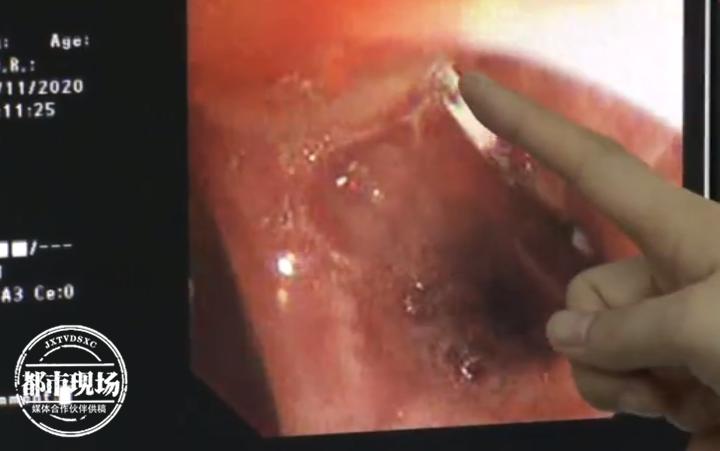

经过CT检查,医生判断针头不是掉进了食道里,而是掉进了气管里。11月9号,医生紧急为李波进行了气管镜操作。手术用时不到五分钟,医生就将一根3、4厘米长的针头状异物从李波的气管内成功取出。

医生:“我们发现这根针的时候,它已经在气道里存在四五天,针尖已经刺破了气道的黏膜,在局部形成了血肿和肉芽组织样的增生。时间长可能形成反复的感染,出现肺感染,甚至是局部肺扩张,影响呼吸的功能。”